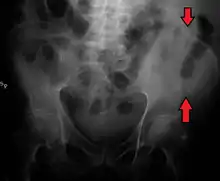

Iliac crest labeled at center right

Iliac crest